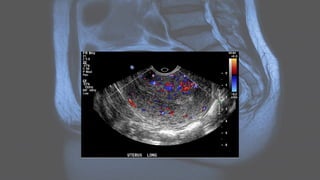

Ultrasound

• Ultrasound is used to diagnose the presence and monitor the growth of fibroids:

• uncomplicated leiomyomas are usually hypoechoic, but can be isoechoic, or even

hyperechoic compared to normal myometrium

• calcification is seen as echogenic foci with shadowing

• cystic areas of necrosis or degeneration may be seen

• Venetian blind artifact may be seen but edge shadowing +/- dense posterior

shadowing from calcification is also typically seen 17